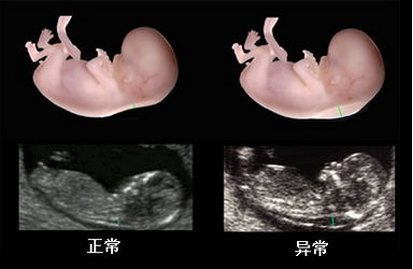

孕早期的系统彩超检查的黄金时间为孕11-14周,这个时候可以通过颈后透明层排除宝宝先天愚型和智力缺陷,而孕晚期系统彩超黄金时间是30--34周,可以对胎儿进行全身系统检查,但具体的检查时间,还是应该根据孕妈妈自身情况来决定,同时,孕妈妈要注意选择一家专业的医院进行系统彩超,才能够达到预期的检查效果。

在检查过程中医生会仔细的对脊椎、头颅、内部、腹部等身体内部各器官进行逐一检查,全面的排查可能存在的异常。

★清晰,排除胎儿先天性疾病:多方位、多角度的观察宫内胎儿的生长发育情况,排除宝宝智力以及先天愚型。